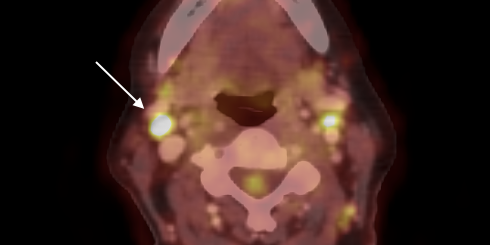

Tämä tapaus havainnollistaa, kuinka intraoperatiivista PET-CT kuvantamista voidaan hyödyntää tuottamaan tietoa kirurgille heti onko esimerkiksi oikea imusolmuke resekoitu histopatologista arviota varten. Tässä tapauksessa potilaan diagnoosia hidasti ensimmäisen biopsian tulos, sillä resekoitu imusolmuke antoi negatiivisen histopatologisen tuloksen. Kuitenkin ^18F-FDG:llä tehty PET-CT tutkimus paljasti epäilyttävää metabolista aktiivisuutta useissa imusolmukkeissa, vaikka ilmeistä sairautta ei ollut havaittavissa. Päädyttiin ottamaan intraoperatiivinen PET-CT kuvantaminen avuksi näytteen otossa ehkäisemään turhia ylimääräisiä biopsioita. Kirurgi poisti oikean imusolmukkeen, joka varmistettiin käyttämällä AURA 10:n korkearesoluutioista PET-CT kuvausta. Histopatologinen analyysi osoitti näiden biopsoitujen imusolmukkeiden olevan angioblastista T-solulymfoomaa.